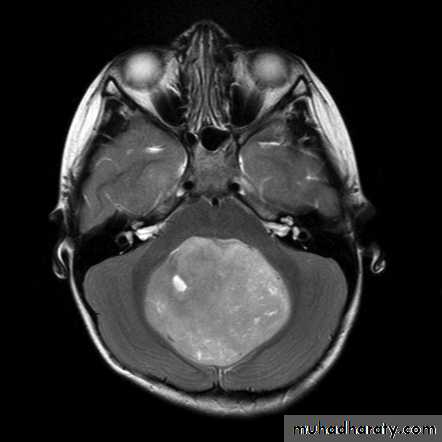

MEDULLOBLASTOMA AXIAL MRI